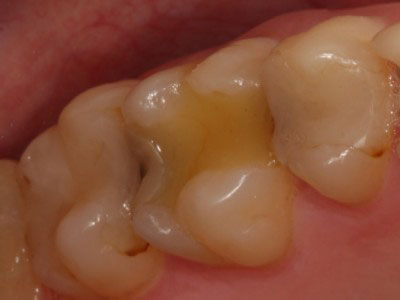

Ко мне обратилась пациентка с просьбой попробовать «спасти» нижний 6-ой зуб от удаления. Вот так он выглядел в полости рта.

Что мы здесь видим? Ну, во-первых, напрочь отсутствующую анатомию зуба. Огромная полость заштукатурена (другого слова и не подберешь) без малейшей попытки создать на зубе необходимый для жевания рельеф поверхности с бугорками и бороздками между ними. Через материал просвечивает анкерный штифт, который призван удерживать эту «нашлепку» внутри зуба. Во-вторых, по краям пломбы заметно прокрашивание границы, т.е. пломба уже давно негерметична, а, значит, внутрь просачивается микрофлора полости рта, вызывая рецедив кариеса и воспалительный процесс в костной ткани вокруг корня. В-третьих, мы можем видеть только 2 сохранившихся стенки собственного зуба, которые к тому же изрядно истончены. Учитывая, что зуб давно мертвый, методика реставрации явно выбрана неудачная. Да и исполнена при этом весьма скверно. Дело в том, что наши жевательные зубы испытывают достаточно серьезные нагрузки при жевании (по разным данным около 100 кг на см2), и оставшиеся тонике стеночки в любой момент могут треснуть. Нередко трещина уходит глубоко под десну и в итоге зуб приходится удалять. Поэтому если зуб депульпирован и имеет значительные разрушения (как в нашем случае), то его нужно обязательно восстанавливать коронкой. Только в этом случае Вы будете застрахованы от любых неприятных сюрпризов. Но для данного зуба это только полбеды. Не меньшая проблема содержалась и внутри.